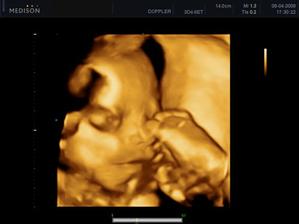

- 5.1.2009 screening dopadl dobře a viděla jsem mimíse jak krásně hýbal ručičkama

- další kontrola a tripple testy (17+3). UTZ v pořádku, výsledky krve budou při další kontrole. a konečně máme potvrzeno pohlaví - JE TO KLUK!!!! dokonce jsem dostala i fotku pindíka tak jí ukazuju všem v okolí 🙂). objednala jsem se k zubaři, na EKG a internu. velký UTZ + další kontrola 3.3.

- 3.3. kontrola v pořádku, byla jsem na 1. velkém UTZ - tam je také vše v pořádku a mimís roste jak má